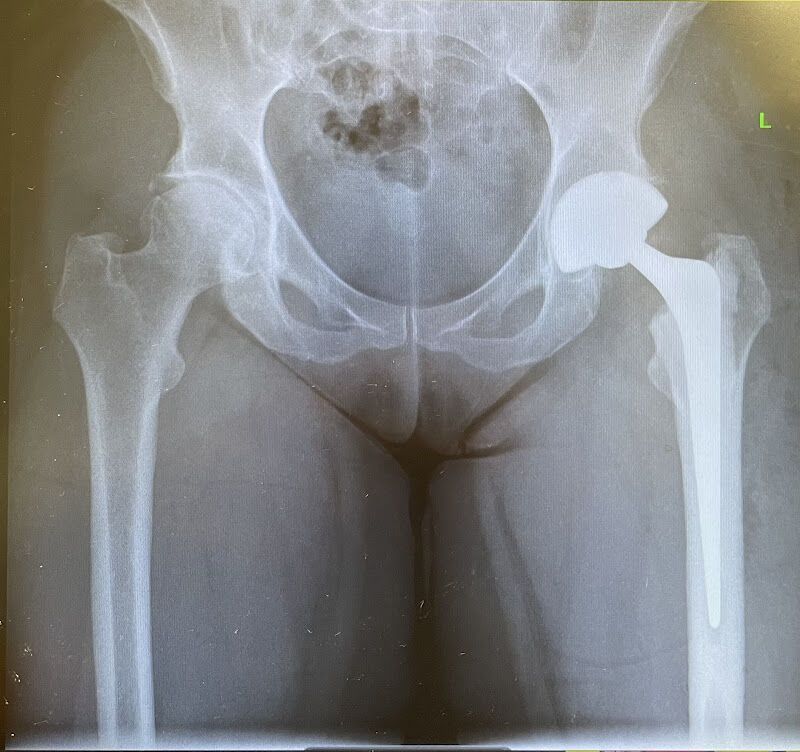

Mark is a Consultant Orthopaedic Surgeon. He specialises in Hip, Knee and trauma surgery. He offers a full range of Hip surgery including small incision hip replacement, hip resurfacing, and revision (redo surgery) hip replacement. He also performs knee replacement and keyhole knee surgery. His other interest is complex trauma of the upper and lower limbs, and in particular fractures into the joints and fractures of and around joint replacements.

Foto van Mr Mark Edmondson